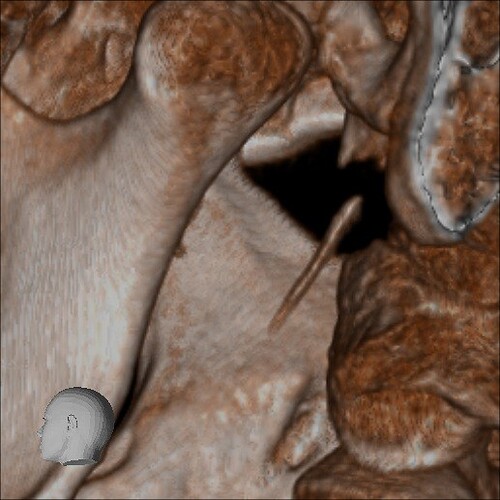

Below are some screenshots from my Cone Beam CT scan and the report linking possible ES. I have more Regular CT scans I could possibly share and/or if you would like me to get possible better angles from the Cone Beam CT scan let me know. But as of right now I’m at a loss as what to do going forward. I do have an MRI with and without contrast of the Cervical Spine Scheduled, but that’s due to the doctor’s (the doctor that dismissed it as ES and one doctor that wants to follow up and learn more on it) wanting it.

- Now onto this year, I finally got better back to full health in late November early December 2024 and sadly started to get another sinus infect in January and still no answers to why. I just happen to be watching YouTube when a Dentist had said that your teeth could be linked to sinus issues causing sinus infections and normally the only way to tell if this is the case is to get a Cone Beam CT scan. I then thought this could be another lead to find out why I keep getting sick as I did when I was 10 have my first top premolar on my left side removed against what I wanted as they said my teeth were too crowded and it needed to be removed so I could have braces (which that dentist didn’t even do my braces anyway). But I thought when he removed it if a small piece of the root was still in there as he just broke out the tooth without removing it via surgical means that that could cause an abscess in my Left Maxillary Sinus where infections always start. So, finally I was able to find a place that would give me a Cone Beam CT scan back in February of this year all while I was just starting to get sick from my infection. Anyway, I finally got the report in March and found out oddly my Left side is mostly normal other than mucus polyps, but I have a few other issues (I have attached the report below). This report is where I first found out about Eagle Syndrome as it states I might have Calcified Ligaments and further testing is needed to confirm. It was only after this report and looking up what Eagle Syndrome was that I can say I have almost every symptom that has ever been reported. Sadly, I couldn’t find anyone in my State at the time that work with Eagle Syndrome and when I did was about a week before I found this site and the doctor I did see seemed to dismiss me as another hypochondriac and you can’t have it as you don’t have Vertigo type Dizziness, my styloid are normal length and I don’t have neck pain equivalent to having to be in a neck brace. Not only this she only looked at my CT scan from a week earlier that I had got in Emergency. The Emergency visit was due to the fact at 8PM that night I had pain in my Right Mastoid Bone, and I was starting to get an earache. I went to lay down and took pain meds and an ice pack in hopes to reduce the pain and swelling. I couldn’t sleep due to the pain and came upfront about 10PM. 10:21PM I couldn’t take it anymore and started to stretch my neck and I felt a huge snap and heard a load pop, all the pain just felt like it disappeared. One minute later, I had a massive pain that spread just like when you get an IV that stings, but it felt like someone was trying to murder me and stabbed a knife into the right side of my skull. I was in so much pain that I was hunched over, and we had to have an ambulance called. I thought I was having an aneurism and my mother thought I was having a Stroke (very rare ES Symptom). When the ambulance arrived, they took my vitals, and my blood pressure was 148/110 with a pulse in the high 90’s low 100’s. Luckily the pain had subsided enough that we were able to go to emergency without the ambulance ride, but while I was in emergency the pain had spread to my left side of my head and now felt like someone had taken a clothes iron and stuck it on my head. Any breeze moving my hair was pure agony and I couldn’t lay my head on a pillow without that burning pain. According to emergency though I must have just had a Mastoid Process infection and it burst. Luckily the pain went away by the time I went to the Doctor for ES, but like I said before they were of no help.